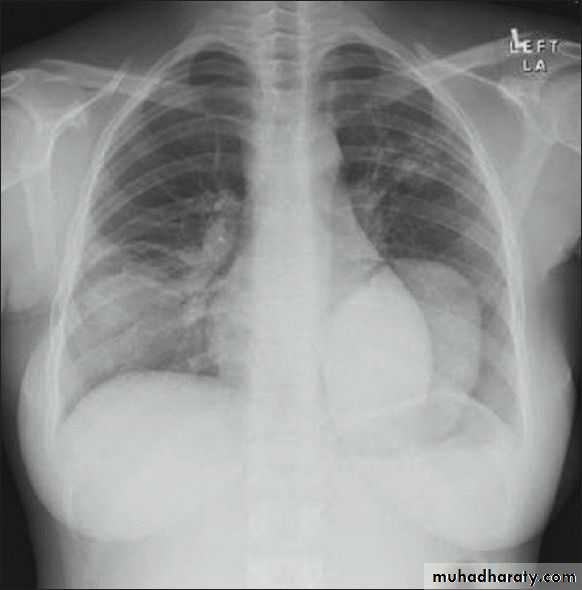

History: dyspnea, weight loss, dehydration with poor immunity